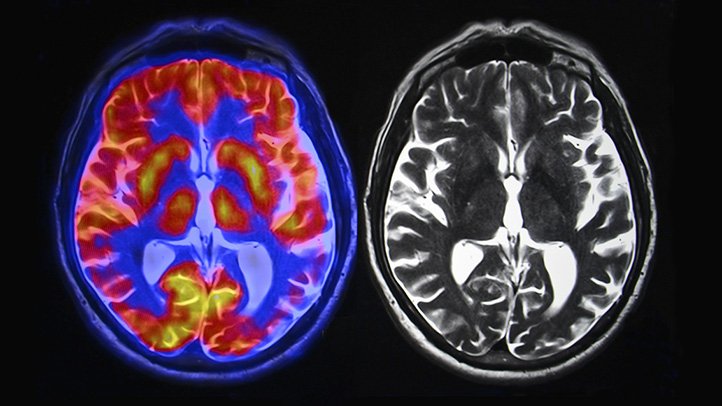

Gadolinium is a chemical element carrying the atomic number 64 and the atomic symbol Gd. Belonging to a group of elements in the periodic table called Lanthanides, the chemical is a rare earth element typically used in microwave applications, color TV tubes, synthetic gemstones, compact discs, and computer memory. This chemical element is widely used as an injectable contrast agent when patients undergo magnetic resonance Imaging (MRI) and magnetic resonance angiography (MRA) scans. The medical community believes that when someone is injected with this dye that the body expels is naturally within a few hours. However, this is not always the case. The chemical agent can also stay in the body for months or years following a single imaging session.

A gadolinium lawsuit may be an option for patients suffering from gadolinium retention and related complications. Gadolinium, used in dyes to increase the clarity of MRI and MRA scans, can create chemical element retention in the body, Therefore, this increases the risk of gadolinium deposition disease and nephrogenic systemic fibrosis. These conditions are accompanied by symptoms that include severe physical pain and cognitive difficulties. Affected patients and their loved ones may be able to file a lawsuit and recover damages.